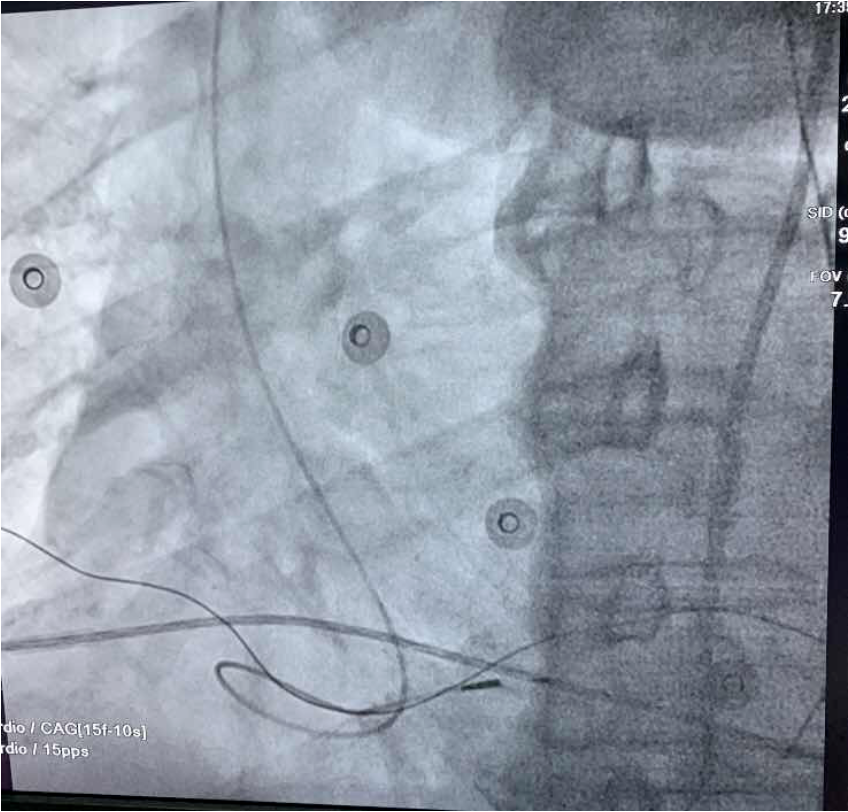

▲左束支起搏

为减少患者的住院率,李润琴主任团队考虑到患者房颤时间长、药物治疗控制心室率效果欠佳,且心脏重构明显、房颤的射频消融术成功率低、复发率高等情况,立刻制定出“房室结改良+ICD起搏、房室结改良+左束支起搏”等几套手术方案。在主治医生与患者家属充分沟通病情后,结合患者及家属的经济状况,最终决定行房室结改良+左束支起搏植入术,最大限度地保持心脏电和机械的同步性,从而达到“双赢”——控制心室率及改善心衰发生。手术过程顺利,李润琴主任团队通过准确的定位,娴熟的手法,还给患者一颗“强心脏”。